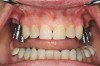

Figure 11  Note the absence of bone at the facial surface of the implants. A hard-tissue graft should be considered.

Figure 11

Figure 12  Proper gingival contours following placement of the implants and subsequent hard-tissue graft.

Figure 12